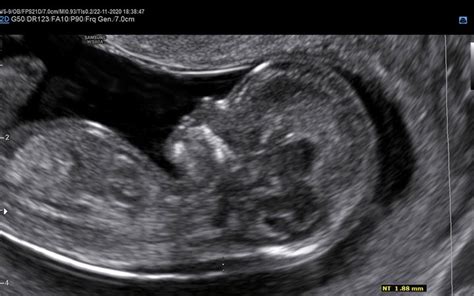

Nuhalna svetlina je v bistvu zbirka tekočine, ki se nahaja v podkožju na zatilju ploda. Na ultrazvočni sliki je to področje videti kot svetlejša črta v primerjavi z okoliškim tkivom, od tod tudi ime "svetlina". V določenih tednih nosečnosti je prisotnost te tekočine normalna, vendar njena povečana debelina lahko nakazuje na določena tveganja. Povišana vrednost nuhalne svetline je pogosto posledica slabšega razvoja limfatičnega sistema ploda, kar je lahko povezano z nekaterimi kromosomskimi napakami, kot so Downov sindrom (trisomija 21. kromosoma), Edwardsov sindrom (trisomija 18. kromosoma) in Patauov sindrom (trisomija 13. kromosoma). Večja meritev nuhalne svetline lahko nakazuje tudi na večje tveganje za razvojne nepravilnosti, predvsem srčne napake. Če je velikost nuhalne svetline nad 3,5 mm, je priporočen podroben pregled otrokovega srca v drugem trimesečju nosečnosti.

Sam ultrazvočni pregled nuhalne svetline vključuje več ključnih meritev in ocen. Osrednja je meritev debeline tekočine na plodovem zatilju. Poleg tega ginekolog izmeri še velikost ploda (razdaljo od temena do trtice, CRL), njegovo srčno frekvenco, preveri prisotnost nosne kosti in opravi zgodnjo morfologijo ploda. Pri zgodnji morfologiji sistematično pregledamo ključne organe in strukture ploda v prvem trimesečju, kot so glavica, možganske strukture, srce, želodček, mehur, okončine in hrbtenica. Pri izračunu tveganja se upošteva tudi starost nosečnice, saj se tveganje za kromosomske nepravilnosti z leti povečuje. V nekaterih primerih je mogoče z manjšo stopnjo zanesljivosti napovedati tudi spol otroka, vendar natančna ugotovitev v tej fazi nosečnosti še ni možna.

Preiskava nuhalne svetline se izvaja v natančno določenem časovnem okviru, med 11 0/7 in 13 6/7 tednom nosečnosti, kar ustreza dolžini ploda med 45 in 84 mm. Pregled je mogoč tudi pri nosečnicah s dvojčki. Običajno se izvaja z ultrazvočnim tipalom preko trebuha (transabdominalno). V primeru slabše preglednosti ali neugodnega položaja ploda se lahko uporabi vaginalno ultrazvočno tipalo (transvaginalno). Nosečnico pred pregledom prosijo, da popolnoma izprazni mehur, kar omogoča boljšo vidljivost. Trajanje pregleda je odvisno od sodelovanja ploda in njegove lege, saj je za natančno meritev ključno, da je plod v pravilni legi.